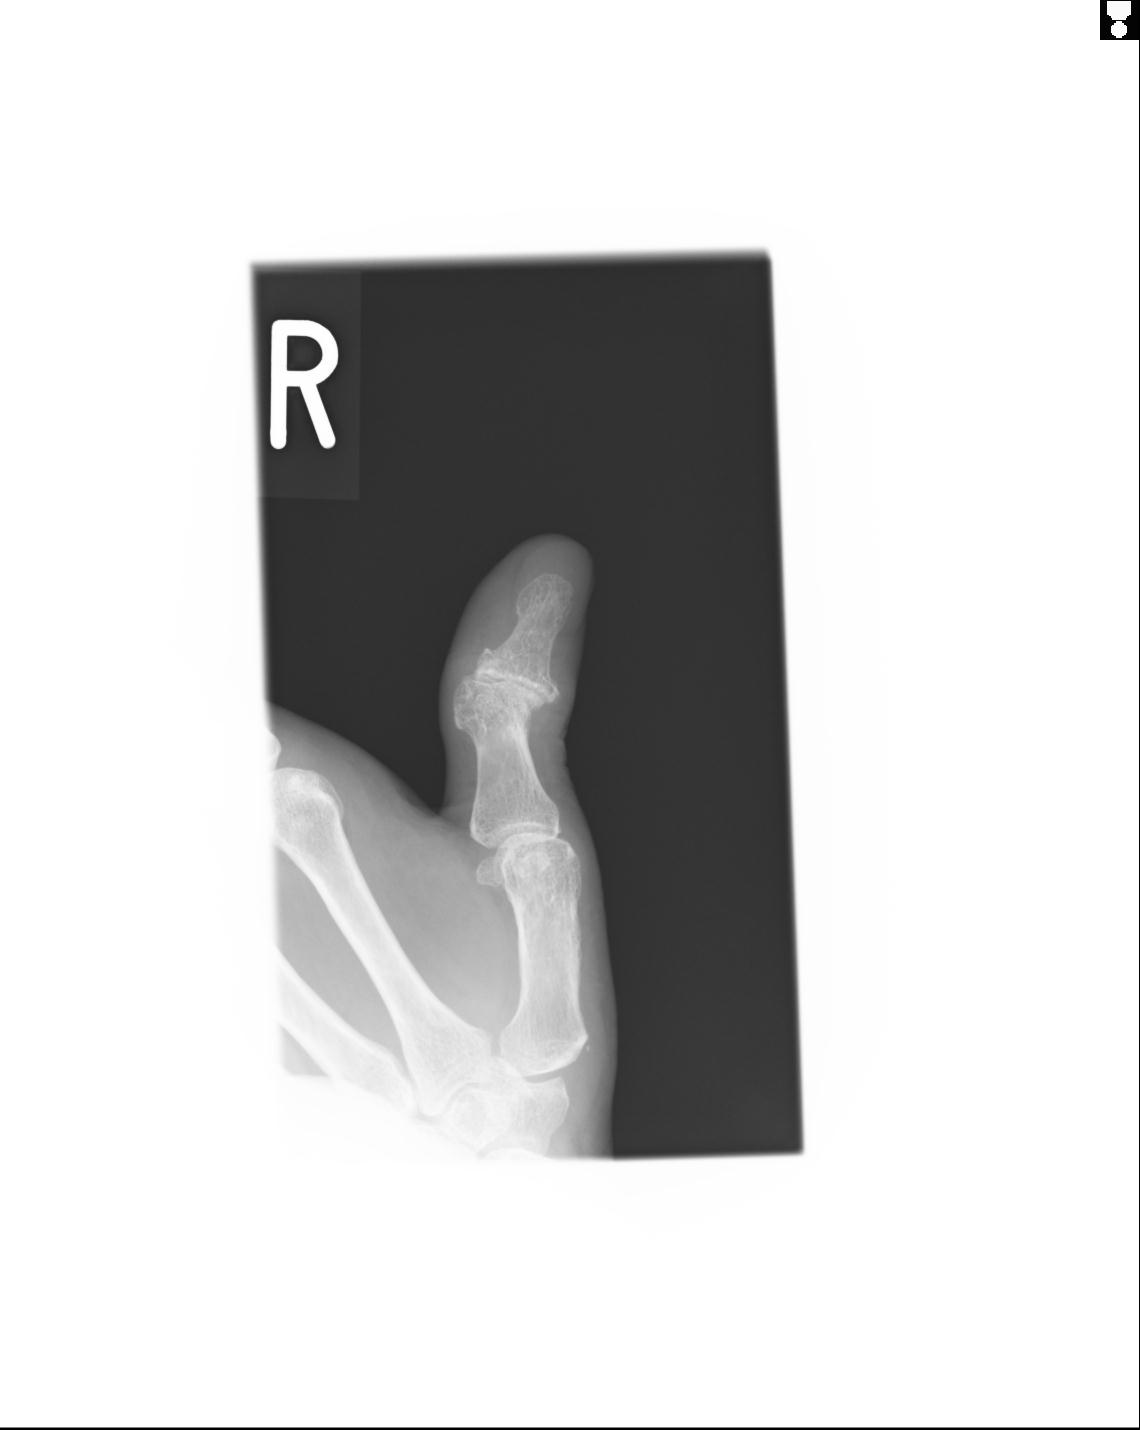

20857 1/11 左手 3R 1/19 4R 55歳男性 小指中節骨骨折

102860 1/21 (4R) 1/26 (4R) 3/15 左手 2R 91歳女性 左環指中節骨

102766 1/5 1/12 左手関節 4R 28歳男性 左橈骨遠位端

50435 1/4 1/15 手関節 4R 17歳女性 右橈骨遠位端

102739 12/30 1/5 左手関節 4R 92歳女性 橈骨遠位端

101290 1/4 5/21 5/20 手関節 2R 17歳男性 橈骨遠位端